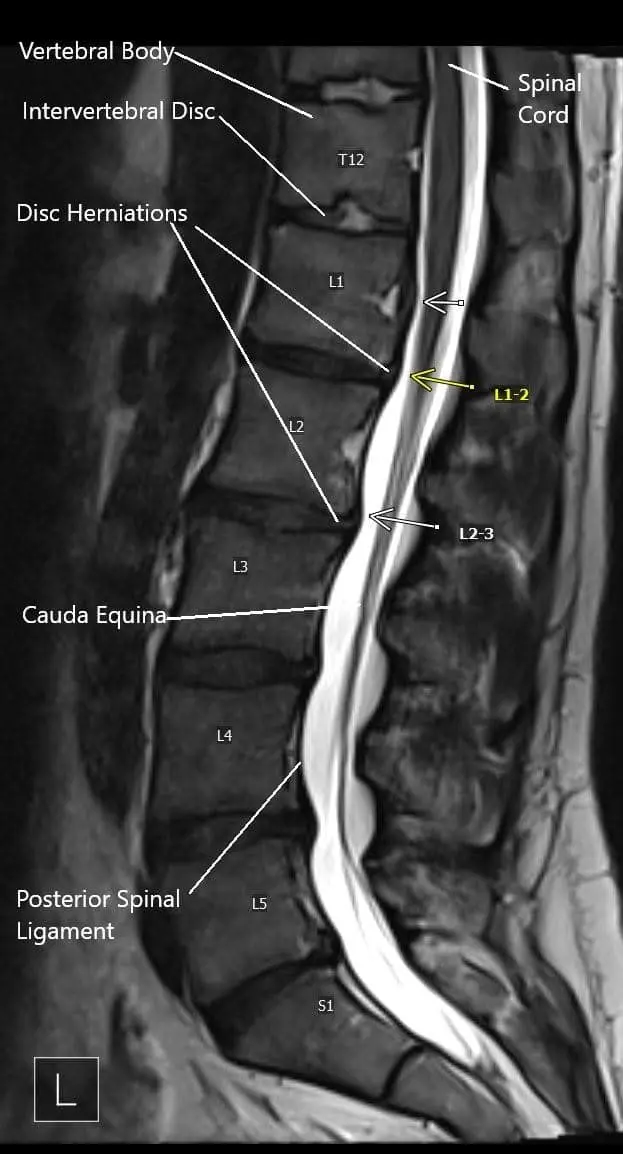

MRI image showing multiple disc herniations.